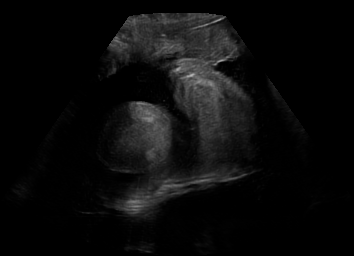

Real in-vivo images. 22 ultrasound sequences were collected using a GE Voluson E8 machine during standard fetal screening exams of 8 patients. Each sequence is several seconds long. We extracted all 4427 frames and resize them to , see Fig. 2 for some examples. The resulting image set was randomly split into training-validation-test sets by a 80-10-10% ratio.